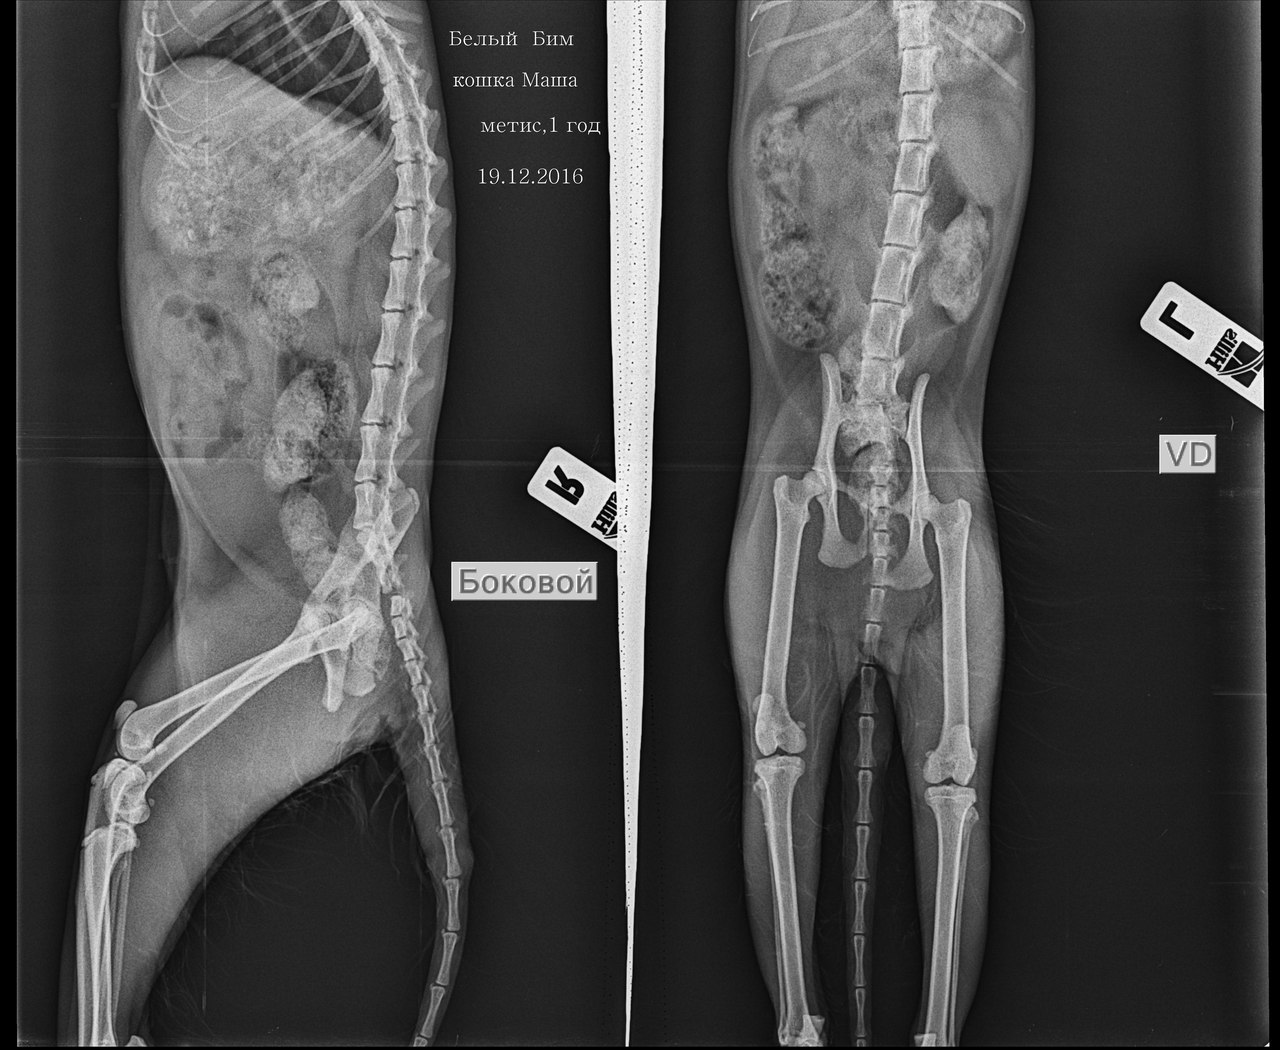

Рентген показал перелом таза со смещением и разрыв хвостовых позвонков.

Сейчас кошечка ослаблена, есть воспаление. Назначен курс антибиотиков, надо её стабилизировать перед операцией. Таз оперировать не придётся, а вот ампутация хвоста необходима.